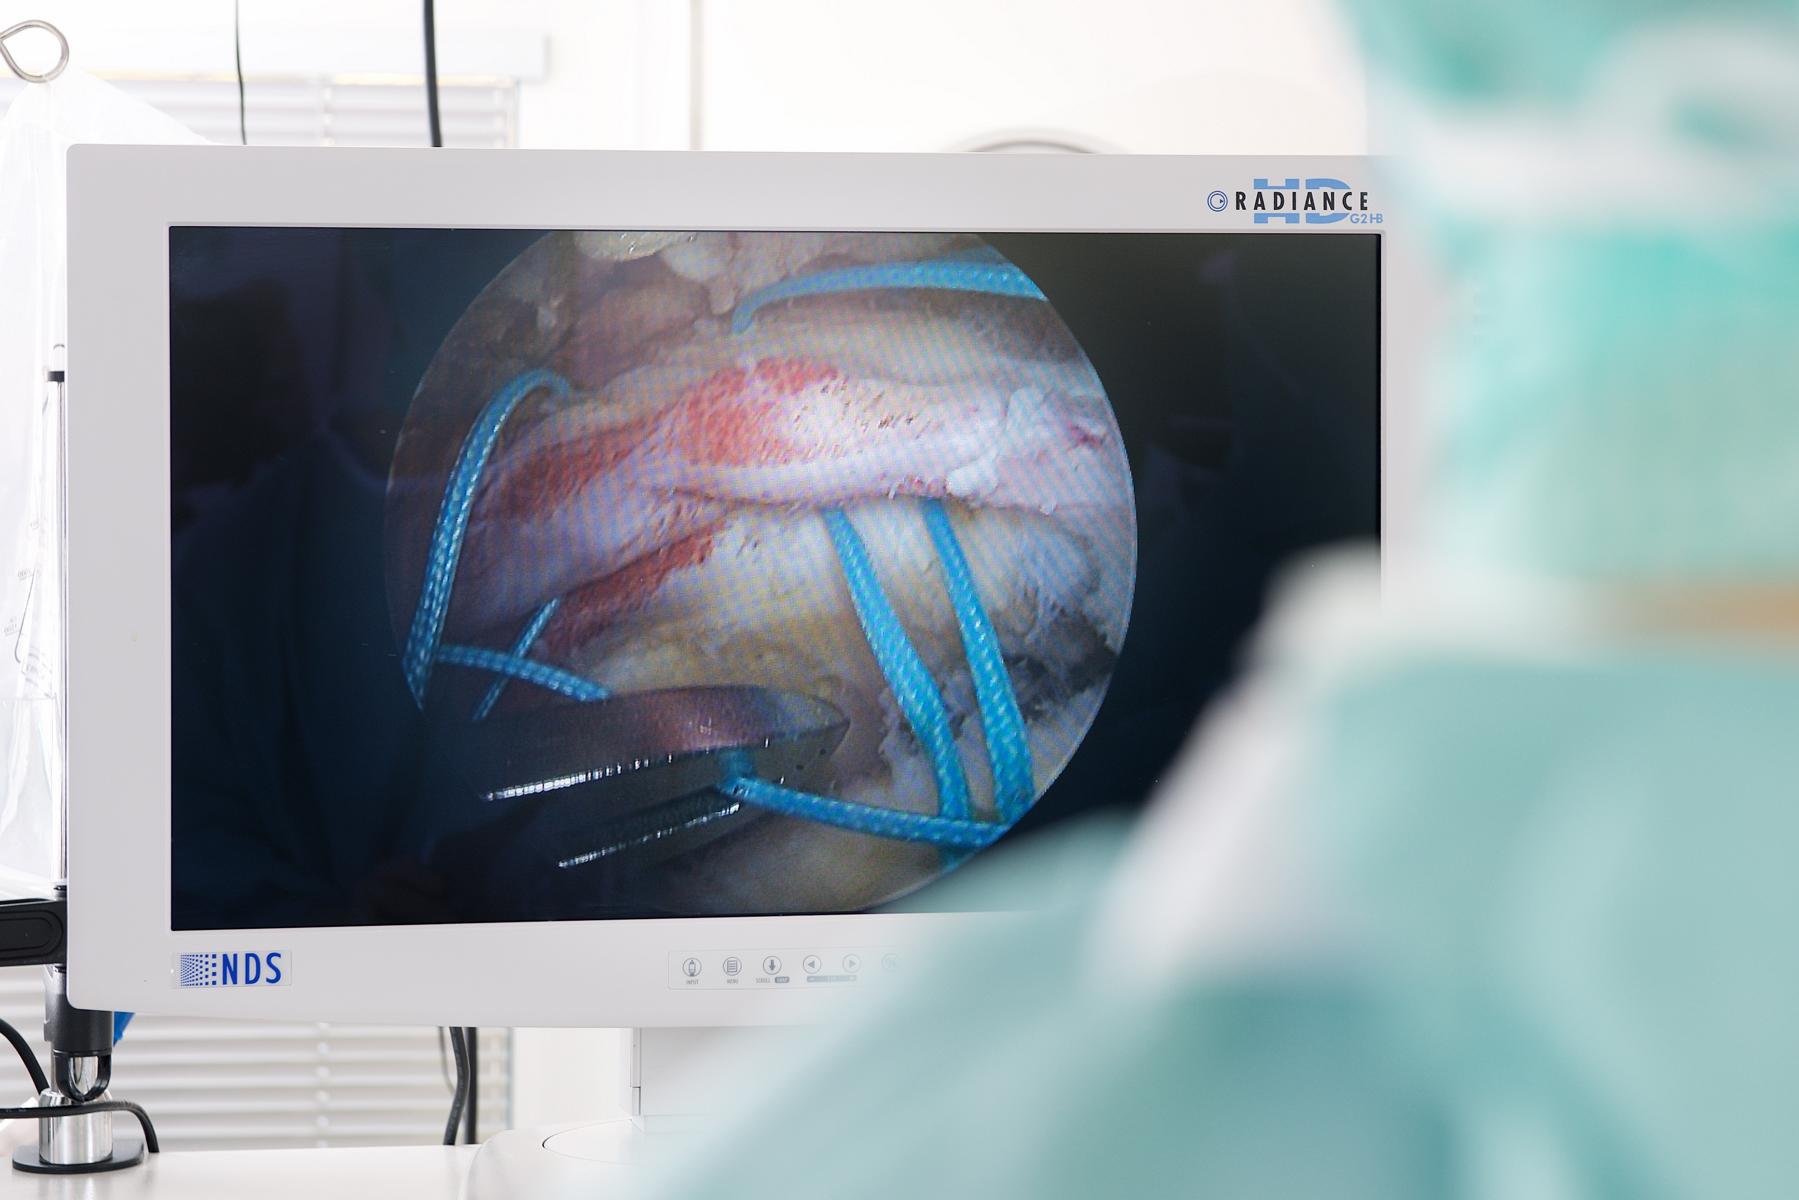

(firmenpresse) - Es geht um nichts Geringeres, als unsere Gelenke. Knie, Hüfte, Schulter, Ellbogen, Sprunggelenk. Dazu Muskeln, Sehnen, Wirbelgelenke. Wenn sich am 2. und 3. Februar Hunderte Orthopäden, Chirurgen, Sportmediziner und Physiotherapeuten auf dem Kongress des BVASK im Düsseldorfer Medienhafen treffen, tauschen sie sich über neueste Therapien, OP-Methoden und Behandlungsansätze aus. Aber nicht nur das. IT-Experten berichten, wie Medizin 4.0 aussehen wird und Insider nehmen die Gesundheitspolitik ins Visier.

Welche Stabilisationstechniken werden am Sprunggelenk eingesetzt, wer profitiert von einer Hüftgelenkspiegelung und wie werden Sehnen funktionell behandelt? Über diese Fragen diskutieren die Fachärzte genauso wie über die Kalkschulter, Patella-Instabilität, Rampenläsionen und Wurzelrisse. Offene Fragen zur Knorpeltherapie und Achskorrektur werden in einer "battle-session" zugespitzt dargestellt.